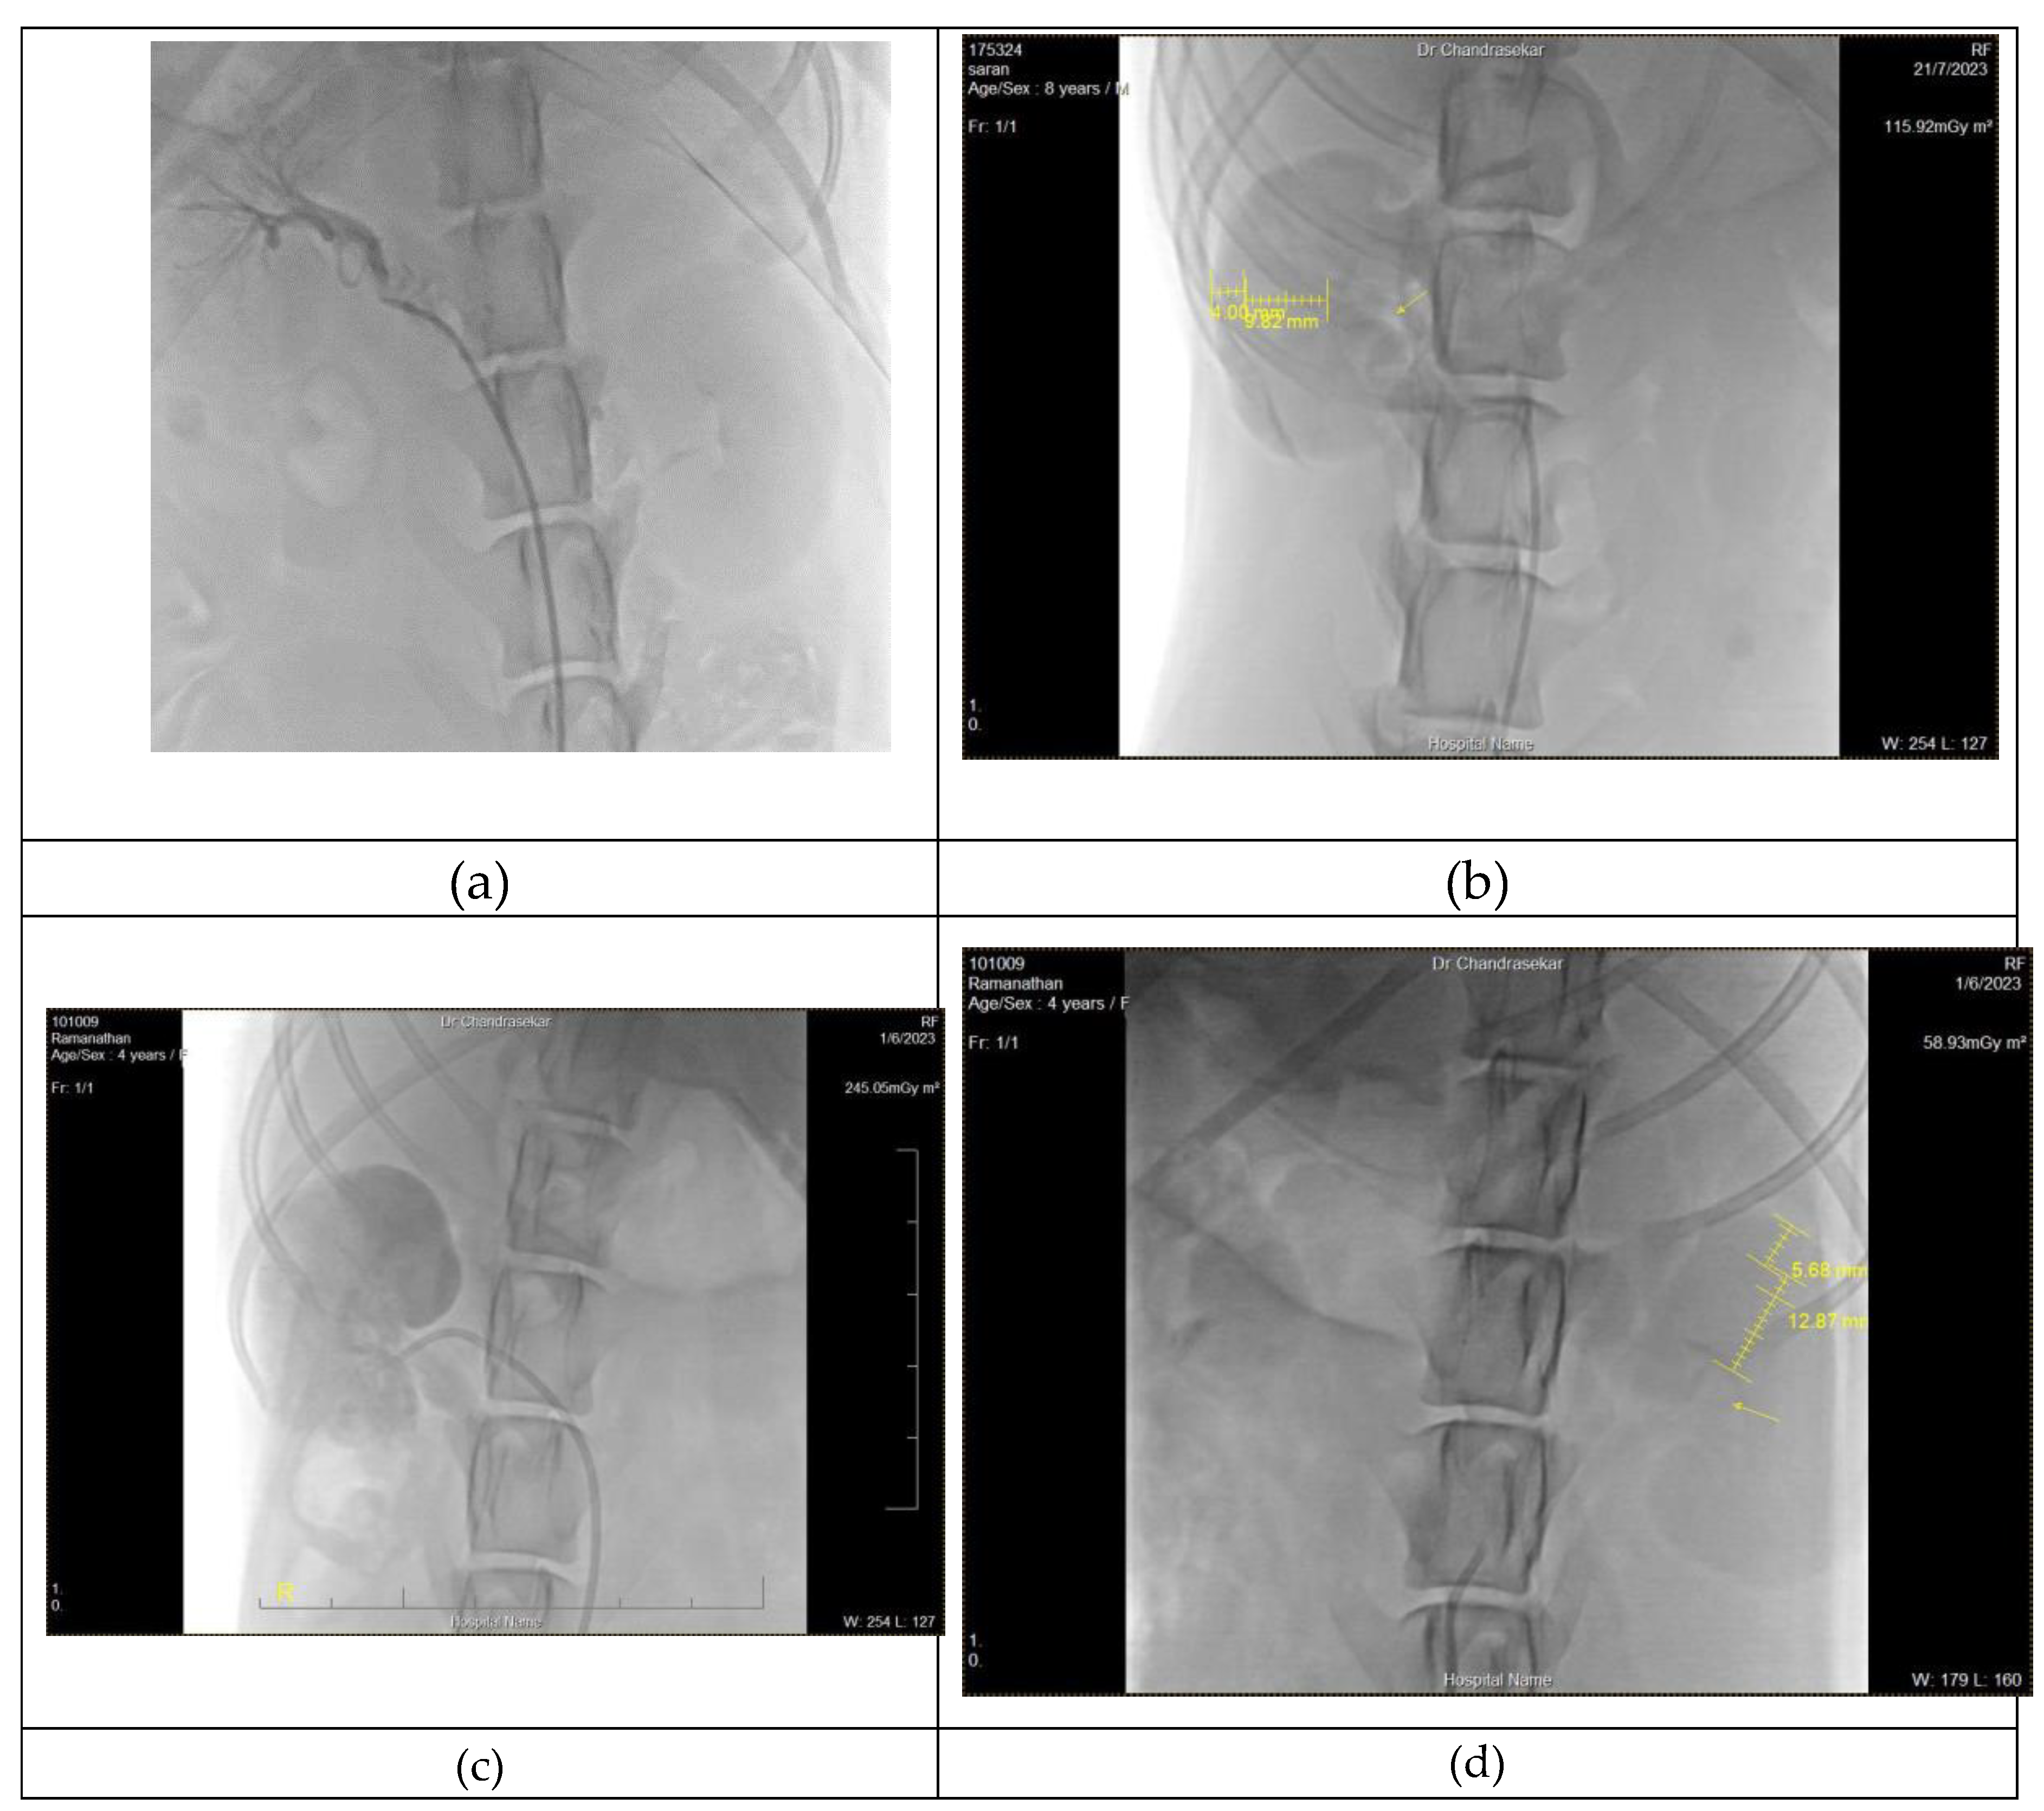

An eight-year-old boxer (case 1) and three-year-old mixed breed (case 2) on selective renal angiogram, the renal cortex medullary ratio (C:M ratio) as 0.40 with thinning of renal medulla. A C:M ratio of 0.45 was observed in six-year-old mixed breed (case4) was which was within the normal range. Under non selective Nephro-angiogram, four-year-old mixed breed (case3 ) had the cortex medullary ratio 0.42, The remaining cases on aortic–renal angiogram show the cortex medullary ratio as 0.38.

In (Case 5 ) and (case 6 ) the mean of cortex medullary ratio of the left kidney was observed as 0.42 (ranging from 0.37 to 0.44) and the right kidney C: M ratio as 0.39 (ranging between 0.36 to 0.45). Renal angiogram measurement of cortex and medullary ratio were tabulated form. (Table 1.)

3.1.2. Vasculature and architectural changes

Selective renal angiogram of Boxer(case 1) and 3y mixed breed (case 2), revealed renal hypoplasia with attenuated thin renal arteries. In case 1 irregular architecture and lack of prominent renal arteries observed on the right kidney, whereas in case 2 renal hypoplasia with attenuated thin renal arteries found in both kidneys. (Figure 2a) Based on findings, it could be either renal atrophy or renal hypoplasia . The angiographic findings of mixed 4y old dog (case 3), revealed reduction in the flow of segmental and interlobular arteries with a symmetrical reduction of parenchyma unilaterally.(Figure 2b)

In selective angiogram of a six-year-old mixed breed(case 4), a stenosis of interlobular arteries and renal hypoplasia was observed on the cranial portion and atrophy(Figure 2c) or hypoplasia of the caudal region of the left kidney.Also in the left kidney, the complete hypoplasia of renal parenchyma was observed. In remaining cases(case 5 & 6), there was a poor perfusion of renal arteries in both kidneys.In case 5 renal hypoplasia was observed in left kidney (fig 2d), while Renal hypoplasia with complete lack of associated interlobular arteries was observed in Case 6 From this study, the approach to the left kidney was easier compared to catheterization of the right kidney and in few cases vice-versa.

Figure 2. Renal angiogram of 6 dogs appeared as (a) Slower filling of interlobular artery; (b) C:M ratio of renal hypoplasia kidney; (c) irregular borders with cranial portion atrophy (d) C:M ratio and appeared as renal hypoplasia.